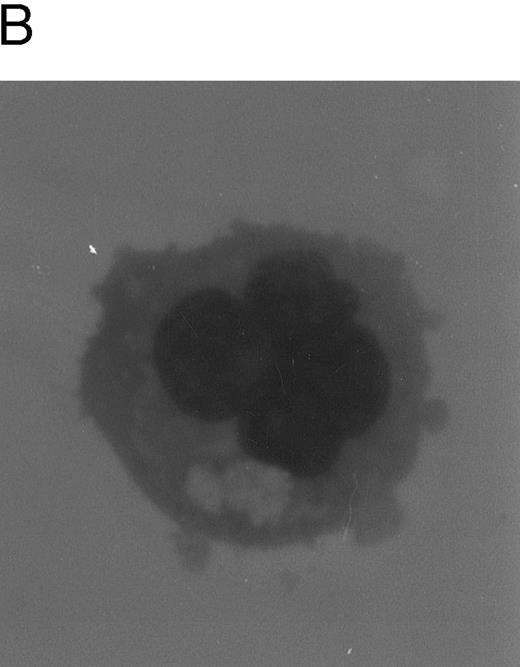

After an initial numerical expansion occurring during the first 12 to 15 days of liquid culture (8-fold increase with respect to day 0), proliferation ceased (Fig 1A) and polyploid megakaryocytes (Fig 1B) became readily detectable at morphologic analysis. The peak of maturation was reached between days 12 and 15 of culture, when more than 50% of the cell population showed a ploidy of 8 to 16 N or greater (Table 1). The remaining 40% to 45% of the cells showing a ploidy of 2 to 4 N was mainly represented by small megakaryoblasts, as judged by high-level expression of αIIbβ3 (Table 2) and by morphologic criteria. By using the same criteria, the fraction of contaminating lymphocytes and monocytes appeared constantly to be less than 5% to 6%.

Evaluation of TPO-induced proliferation and differentiation along the megakaryocytic lineage of CD34+ cells. In (A), viable cells were scored by Trypan blue dye exclusion after various days of liquid cultures supplemented with 100 ng/mL of TPO. Data are expressed as the means ± SD of three separate experiments performed in duplicate. In (B), cytospins were observed at light microscopy after May-Grünwald-Giemsa staining. Original magnification (OM) × 400.